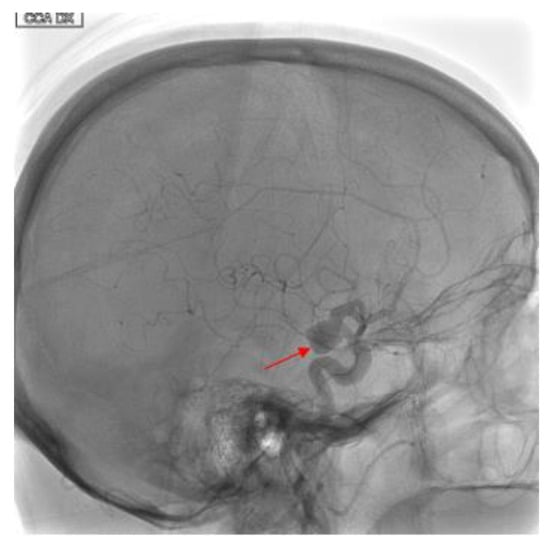

Intracranial Carotid Artery Aneurysm Treatment: First Reported Case of DERIVO®Flow-Diverter Placement by Direct Carotid Artery Puncture

2. Case Presentation